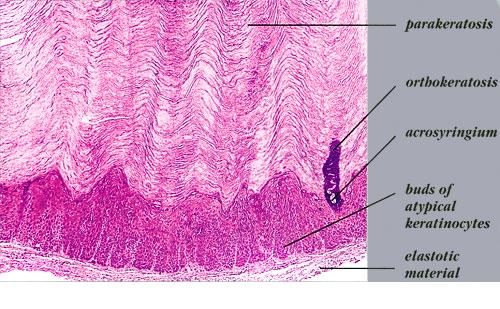

Verrucous solar keratosis = التقران الضيائي المتثألل